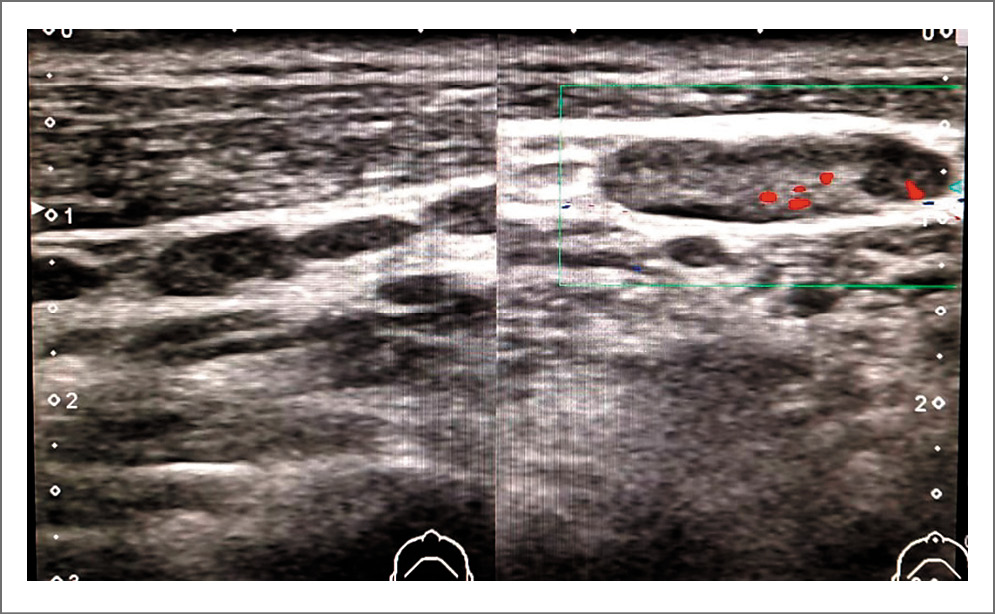

Выполнено ультразвуковое исследование периферических лимфоузлов 08.10.2021; картина представлена на рис. 5–8.

Рис. 6. Лимфоузлы слева: определяются множественные лимфоузлы с неизмененной структурой по ходу ключично- сосцевидной мышцы и в поднижнечелюстной области с максимальным размером 17,7×4,2 мм.